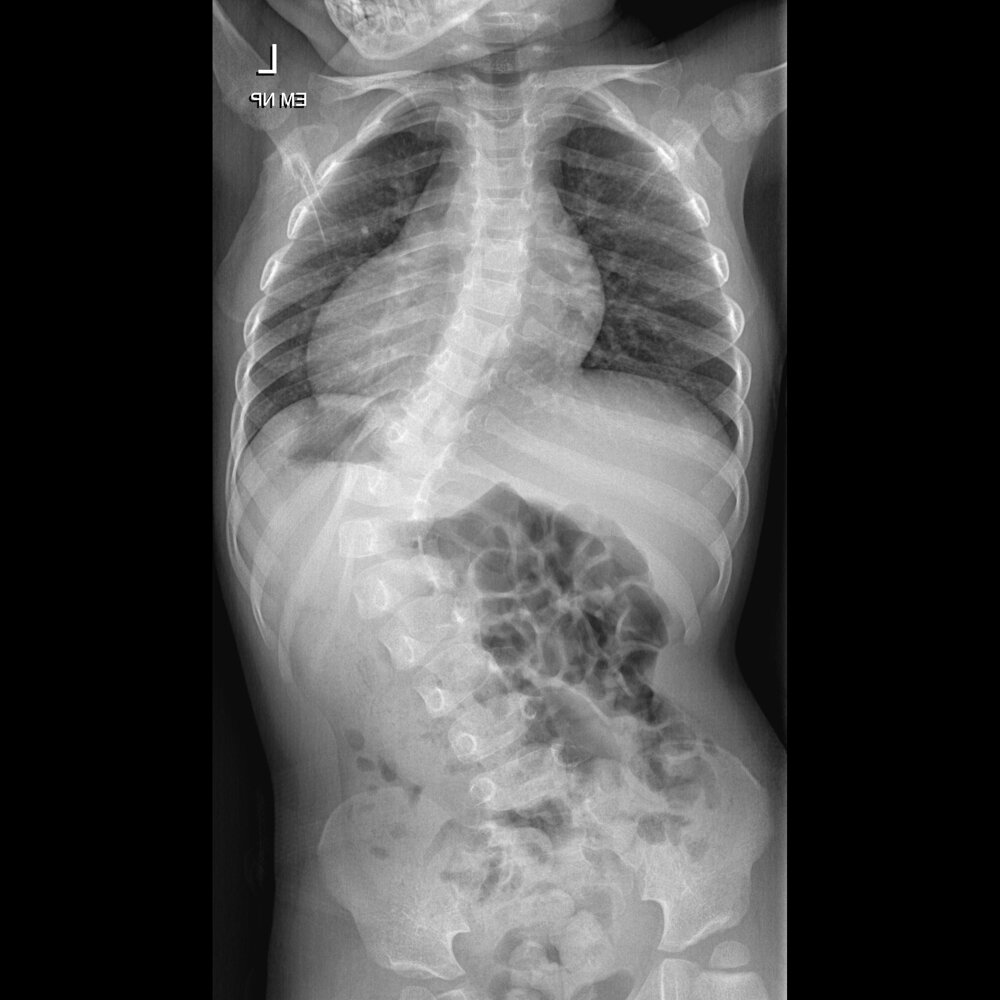

Operácia ťažkej skoliózy

Zdroj: FNsP